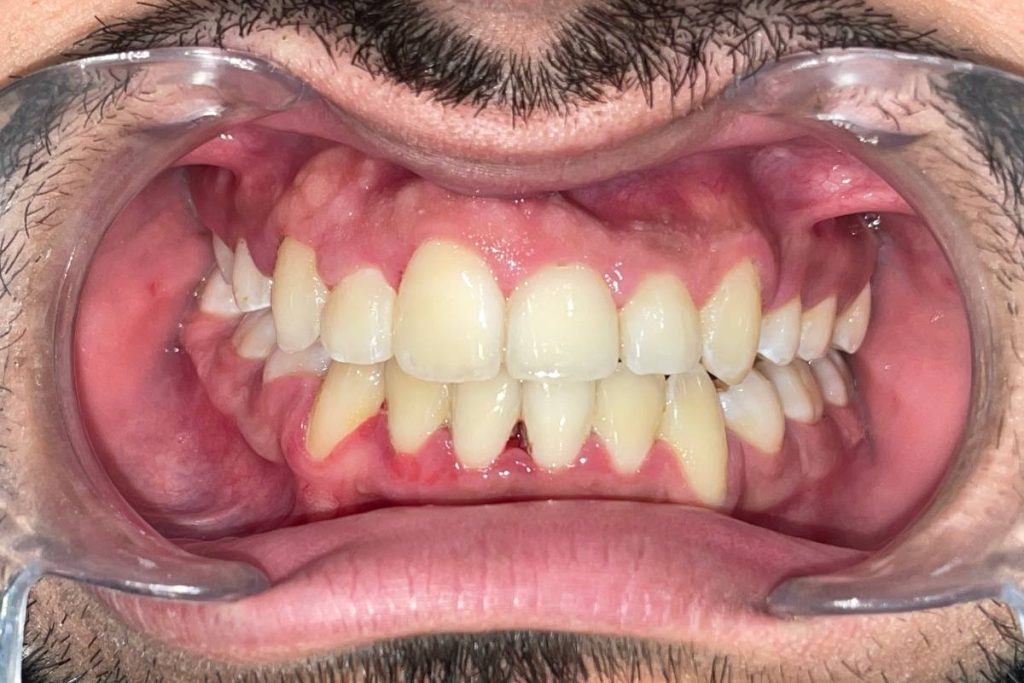

La mejor opción para llevar a cabo la restauración de su sonrisa es a través de una ortodoncia clásica con brackets; con ella recolocas los dientes en la posición correcta y consigues una mordida funcional, además de una bonita sonrisa.

Una vez la ortodoncia puesta, y debido a la falta de espacio por su discrepancia óseo-dentaria, procedimos a la extracción de los premolares tanto superiores como inferiores. Así creábamos el lugar suficiente para “mover” los dientes y conseguir el mejor resultado final.

En una primera estimación, calculamos unos 24 meses para llegar al punto deseado. Pero no nos hizo falta tanto tiempo. Gracias a la buena respuesta del joven, 20 meses fue suficiente para la obtención de los resultados deseados.

Imagen completa del paciente post tratamiento dental.

Si os fijáis, la paleta derecha era (de forma natural) un poco más grande que la de al lado, pero el paciente afirmó que le gustaba esa asimetría y que no quería ningún tipo de talla o intervención en ella. A nosotrxs nos pareció perfecto por que tu boca es única y las singularidades son las que la hace diferente.

Imagen de una sonrisa sana y funcional después del tratamiento.